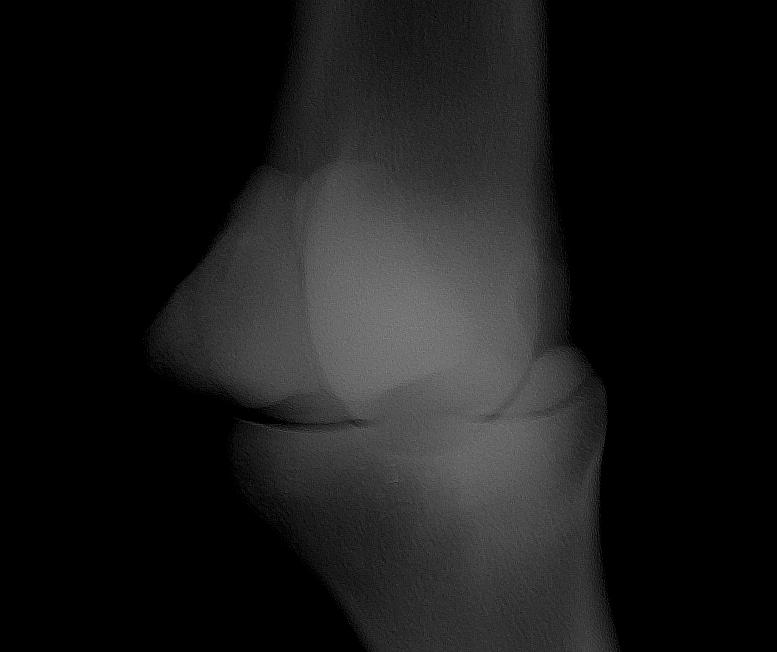

I became a horse mummy to an OTTB 4-year old mare 3 months ago. She is not lame, but I always noticed heat coming from her fetlock. I had x-rays done the other day, and they revealed a bone chip in the joint.

Looking at the x-ray, what's the course of treatment you would recommend?

Left Front Fetlock Lateral View

Thanks for your input christina. Your good experience with surgery of the fetlock is fairly typical. Even horses that do develop lameness from traumatic or OC chips tend to come sound when they are removed. However I believe the large majority of such chips as shown above never cause problems assuming there are no surprises in the other views but once I see the other images I will research this.